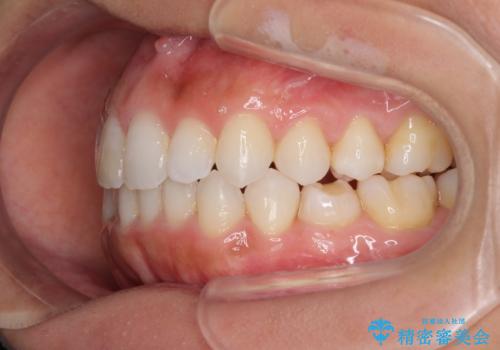

- 上下の前歯のデコボコと奥歯の反対咬合を気にして来院された患者様です。

インビザラインを用い、上下顎ともにIPR(歯と歯の間を削る)により叢生を改善することとしました。

奥歯の反対咬合は、骨格に由来するものであるため、改善できるところまで改善していくこととしました。

治療を長期化させたくないとのご要望があったので、左下の90度捻転した歯は、捻転した状態のゴールとしました。

反対咬合を改善したことで、歯ぎしりしたときの引っかかる感じがなくなり、奥歯への負担を大きく軽減することができました。